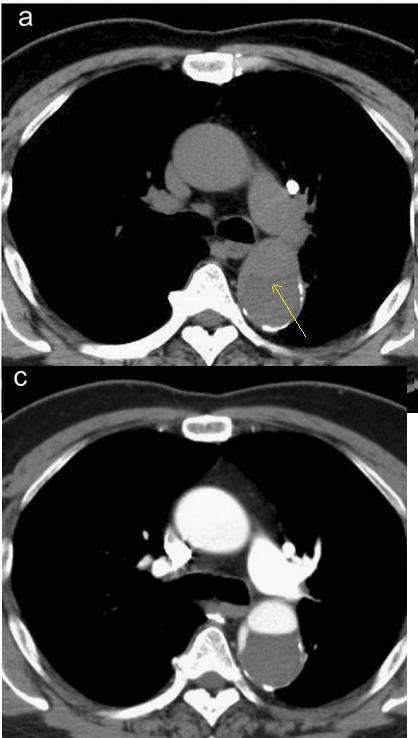

病例9

下面这个CT平扫,似乎有大问题!

图22

什么问题?似乎这里有大问题!

图23

同学,你眼神太好使了!

很可惜,这个不是问题,很多CT平扫都有这种线样阴影!

做个增强CT一看,哇,同学,你不光眼神好,运气也不是一般的好!

图24